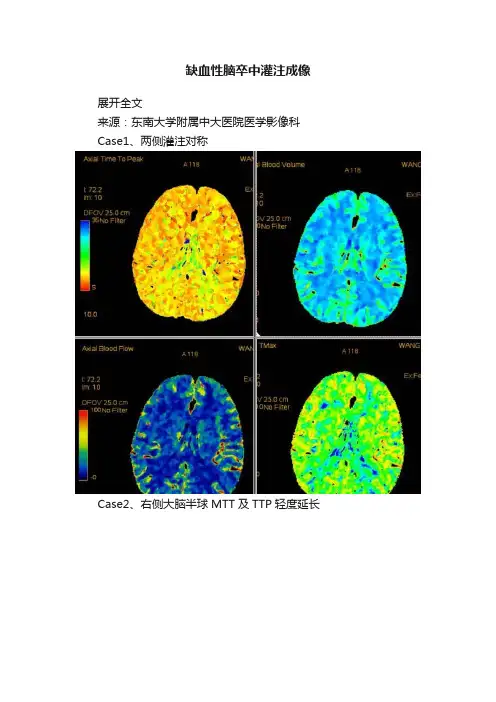

缺血性脑卒中灌注成像展开全文来源:东南大学附属中大医院医学影像科Case1、两侧灌注对称Case2、右侧大脑半球MTT及TTP轻度延长Case3、右侧大脑半球灌注减低,CBV增高,I3-II1期,顶叶梗塞灶Case4、右侧顶颞叶梗塞灶Case5、左侧大脑半球侧枝丰富,过度灌注Case6、缺血半暗带,梗死核心左枕叶缺血性脑卒中灌注成像1、灌注定义:灌注是血流通过毛细血管网,将携带的氧和营养物质输送给组织细胞的重要功能。